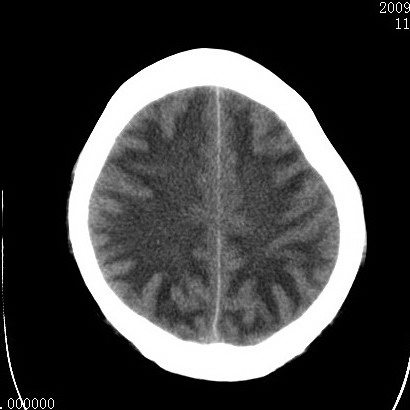

以下是引用余辉在2009-4-9 17:34:00的发言:[br]双侧脑白质对称性弥漫性密度减低,脑室脑沟裂池变小,双侧豆状核对称低密度,脑干对称性低密度,考虑1中毒性脑病2电解质异常(低钾钠等)3代谢异常及维缺乏等,进一步检查。